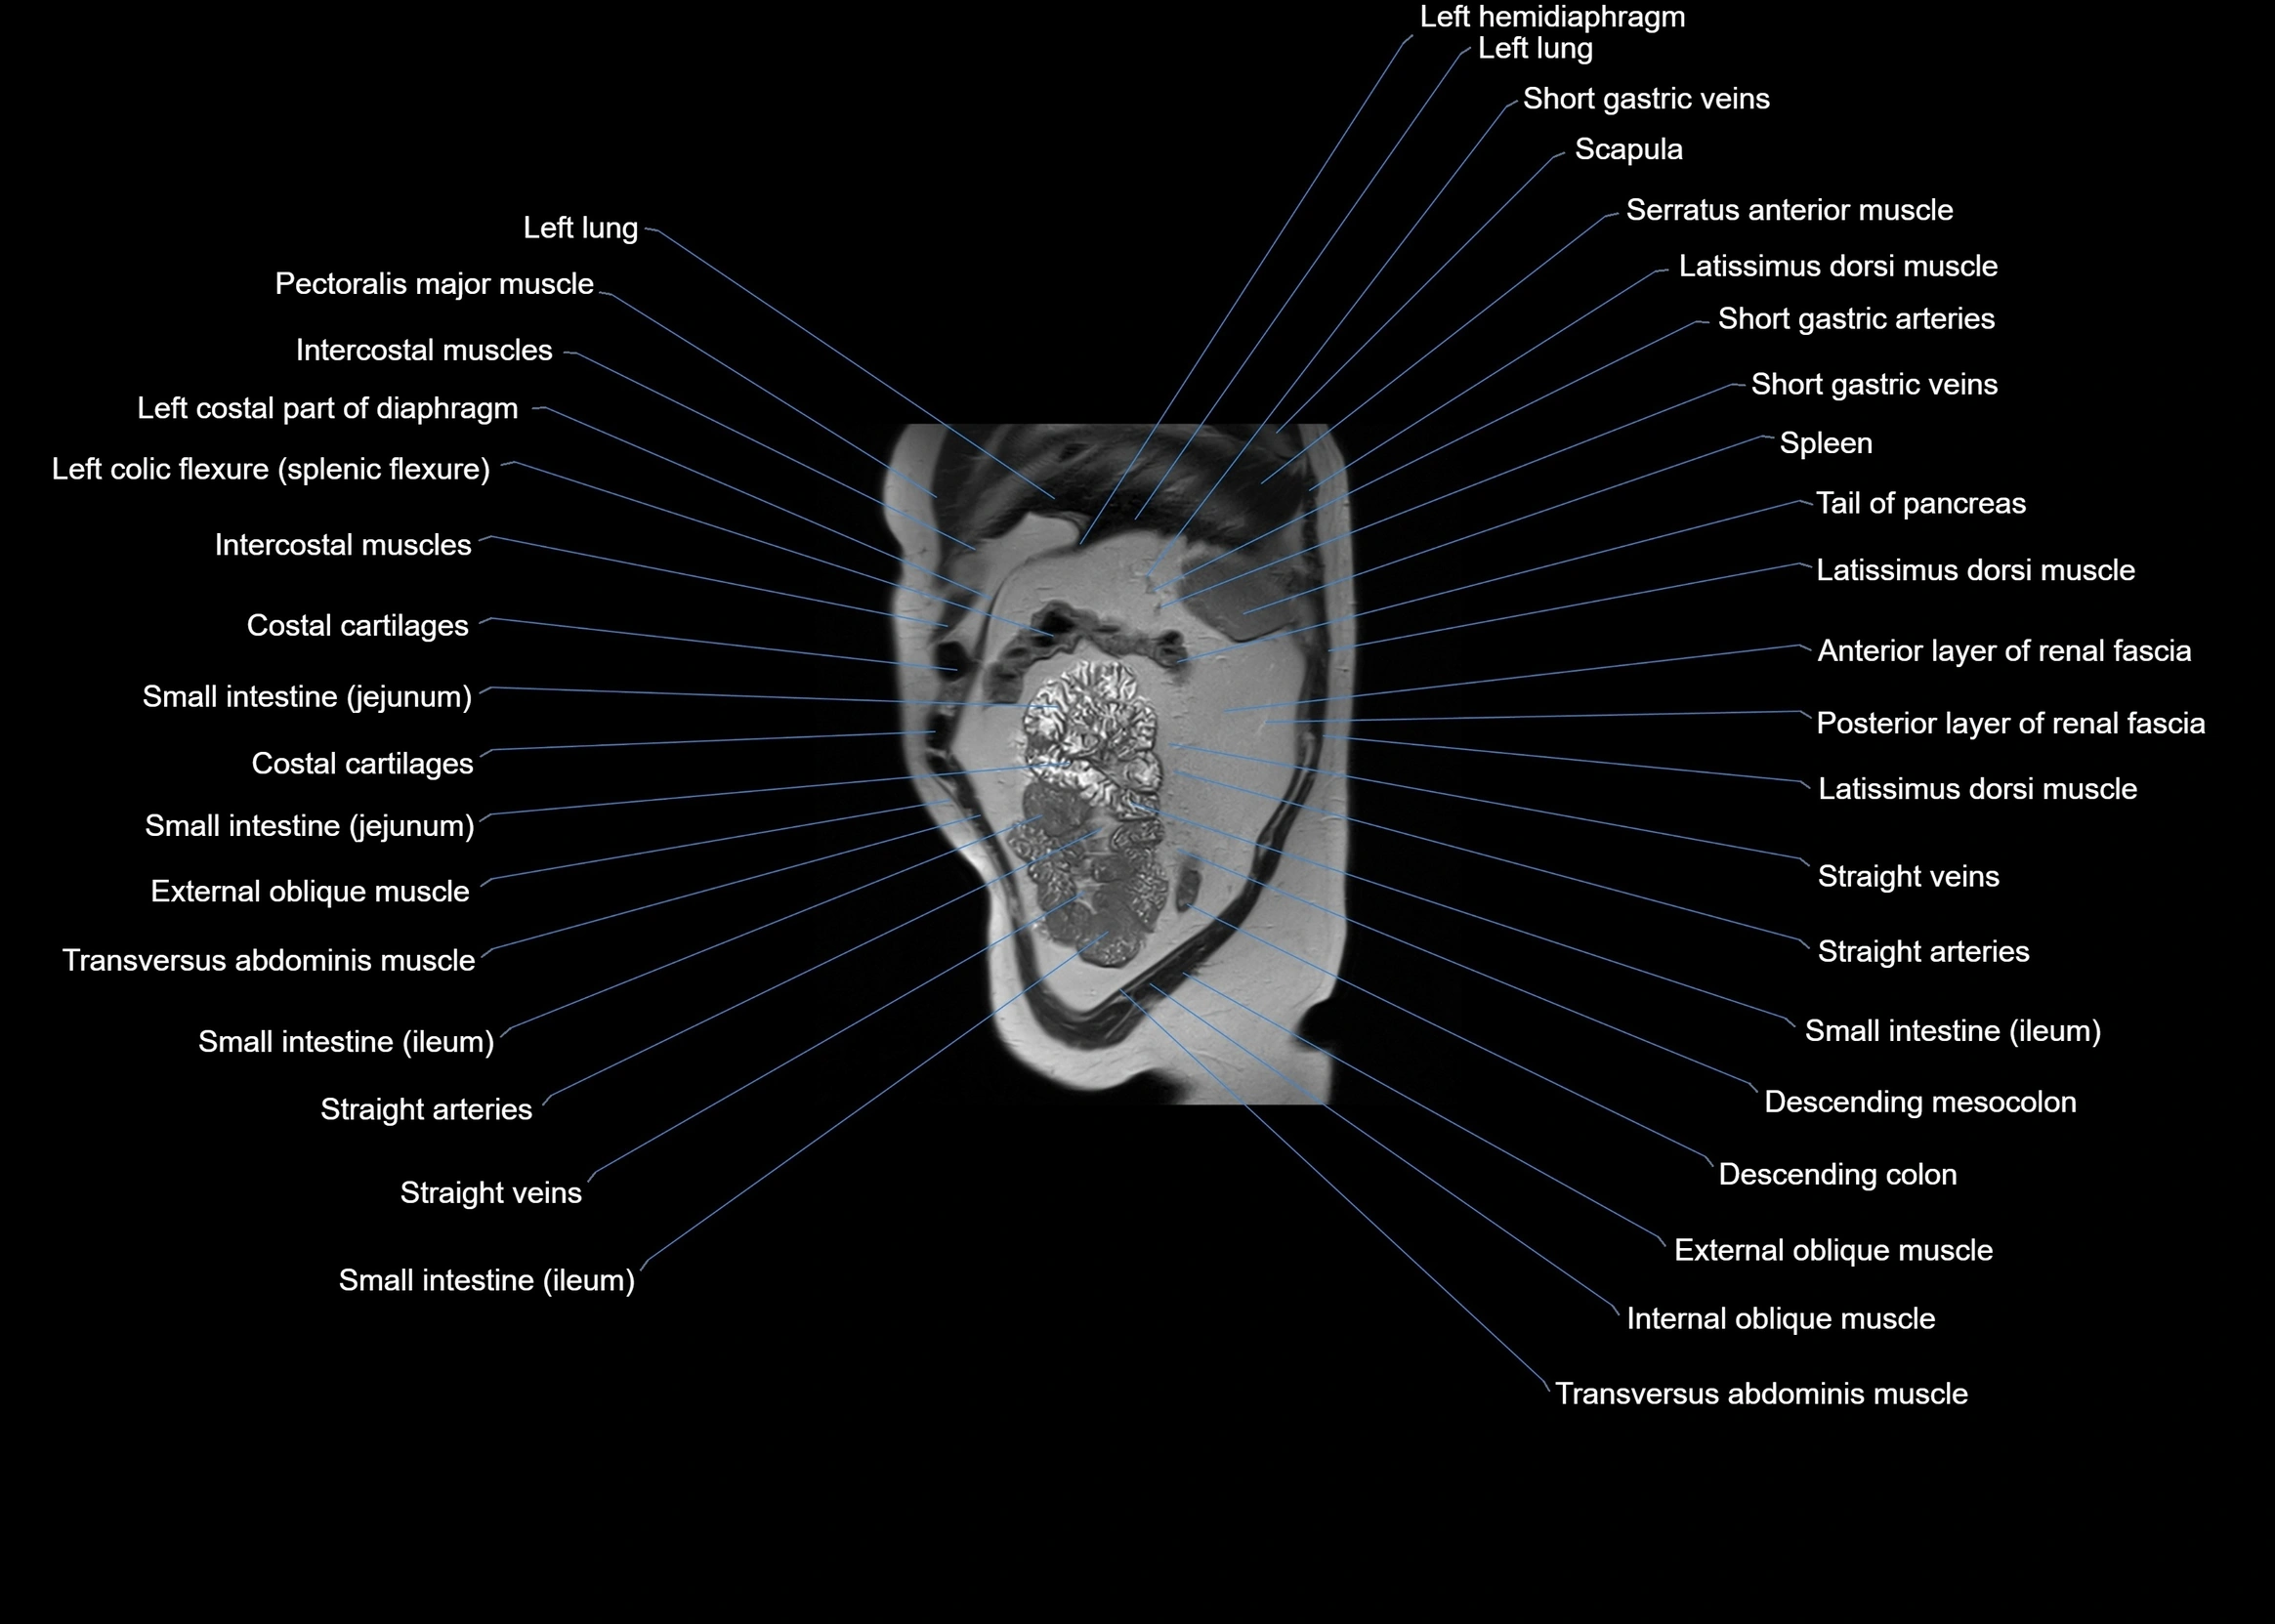

MRI images